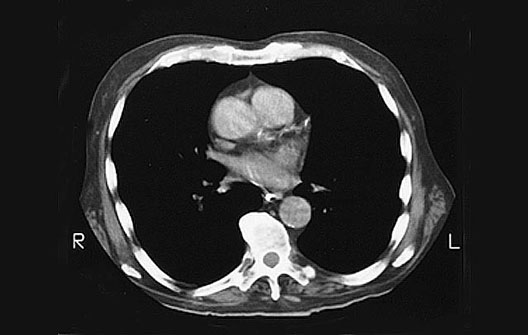

Heart CT

1. Ascending aorta

2. Pulmonary trunk

3. Pulmonary veins

4. Descending aorta